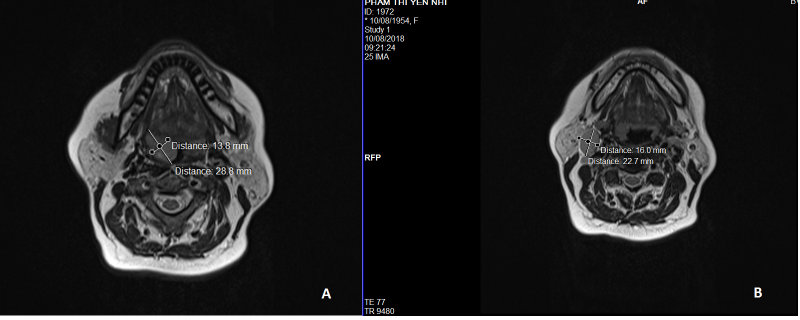

Bệnh nhân nữ 64 tuổi vào viện vì nuốt khó kèm có khối u vùng cổ bên phải. Bệnh nhân không có tiền sử hút thuốc, uống rượu. Qua thăm khám lâm sàng phát hiện khối u amiđan bên phải, kích thước đo được trên MRI vùng cổ - mặt có thuốc cản quang là 13.8 x 28.8mm (hình 1A). Ngoài ra, bệnh nhân có hạch cổ nhóm II và III vùng cổ phải, kích thước hạch lớn nhất đo được là 16.0 x 22.7mm (hình 1B). Bệnh nhân được bấm sinh thiết khối u amiđan bên phải cho kết quả carcinoma tế bào biểu mô amiđan. Theo hệ thống phân loại giai đoạn TNM của AJCC phiên bản thứ 8, bệnh nhân được xếp loại T2N2bMo, tương ứng với giai đoạn IVA. Dựa vào bảng hướng dẫn điều trị NCCN của Hoa Kỳ 2018 dành cho ung thư vùng họng miệng, đối với bệnh nhân có phân loại hạch N2a hoặc N2b, cần được phẫu thuật cắt bỏ khối u nguyên phát vùng họng miệng kèm nạo vét hạch cổ cùng bên hoặc cả hai bên. Vì vậy, bệnh nhân này đã được phẫu thuật vào tháng 8 năm 2018 bao gồm: cắt bỏ rộng rãi khối ung thư nguyên phát vùng amiđan bên phải, kèm nạo vét hạch cổ cùng bên nhóm IIA, IIB, III, IV, V, VI, và bảo tồn tĩnh mạch cảnh trong, động mạch cảnh chung và dây thần kinh phụ (hình 2,3). Thời gian phẫu thuật nạo vét hạch < 1 tiếng. Dịch dẫn lưu sau mổ < 20ml. Bệnh nhân được rút hemovac dẫn lưu vào ngày thứ 2 sau phẫu thuật với lượng dịch dẫn lưu < 5ml. Hậu phẫu ổn định.

Hình 1